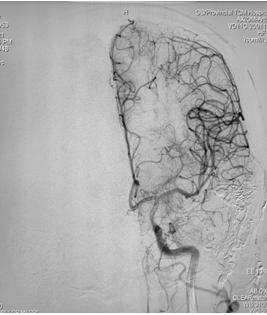

脑病介入科曹骅主任、赵宏廷主治医师先进行左侧颈外动脉血管造影,以明确复杂瘘口,术前造影:颈外动脉中包括枕动脉、耳后动脉、颞浅动脉的多个分支通过硬脑膜向颅内静脉形成异常引流,栓塞术难道很大。

手术过程:术中采取弹簧圈辅助填塞,Onyx液态胶多支供血动脉分次栓塞治疗措施,由于供血动脉纵横交错,手术难道可想而知,经过4小时的艰难努力,于18:30手术结束,术程顺利,成功帮助患者填塞了动静脉瘘,为患者解决了病痛。